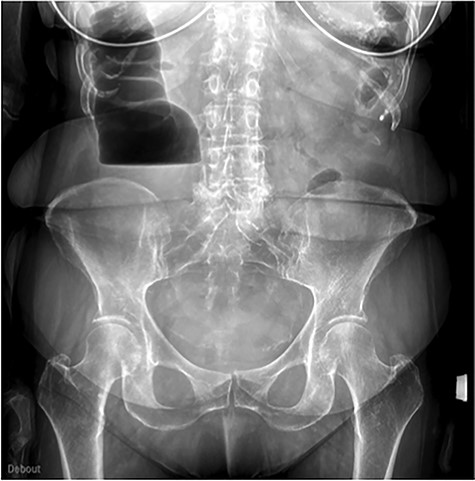

The scanner demonstrated a colonic occlusion resulting from an incarceration, which was diagnosed as a hernia of Bochdalek containing the hepatic angle of the colon (Fig. 2–4).

CT scan images demonstrating a right diaphragmatic hernia containing intestine.